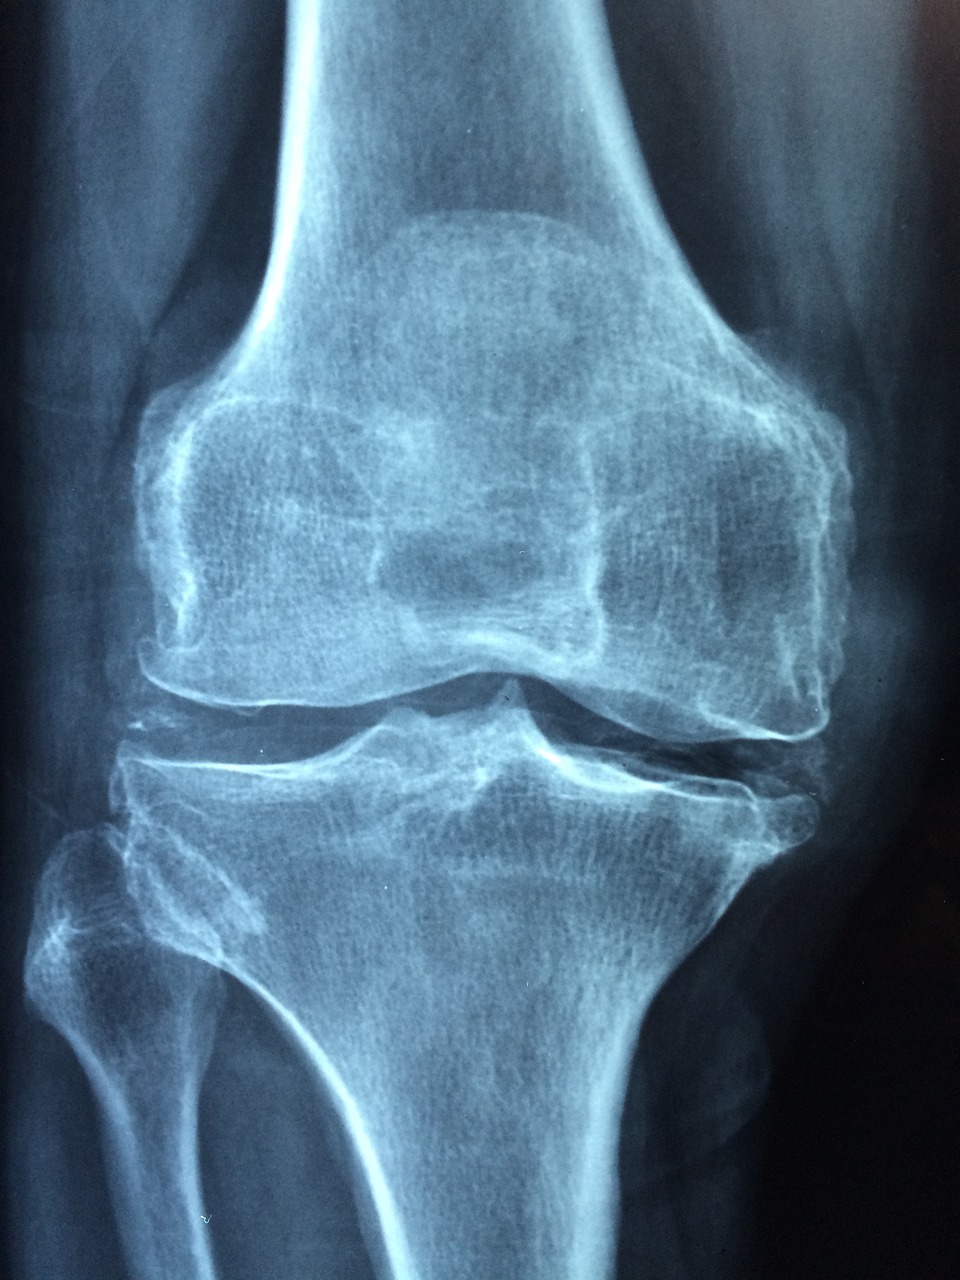

무릎관절은 하지의 상하 관절로, 대퇴골(대퇴아래뼈)과 정강이(경골)의 연결로 이루어져 있습니다. 무릎은 우리 몸에서 가장 큰 관절 중 하나로, 일상적인 활동 및 운동에 중요한 역할을 합니다.

무릎관절의 구조적인 요소는 다음과 같습니다:대퇴골 (Femur):대퇴골은 허벅지뼈로 불리며, 허벅지의 상부에 위치합니다. 대퇴골의 상단에는 무릎관절과 연결되는 무릎머리(무릎판)가 있습니다. 정강이 (Tibia):정강이는 종아리뼈로 불리며, 무릎과 직접 연결되어 있습니다. 정강이의 상단은 대퇴골과 무릎관절을 형성하는 무릎구(무릎플레이트)로 알려져 있습니다. 무릎판 (Patella):무릎판은 손가락 손톱 정도의 크기로, 대퇴골과 정강이 사이에 위치한 삼각형 모양의 뼈입니다. 무릎판은 허벅지 근육과 결합되어 무릎의 움직임을 도와줍니다. 총액판 (Meniscus):무릎 관절 내부에는 두 개의 총액판이 위치해 있습니다. 이들은 반달 모양이며, 대퇴골과 정강이 사이에 위치하여 충격을 흡수하고 관절의 안정성을 유지합니다. 인대 (Ligament):무릎 주변에는 다양한 인대가 있습니다. 대퇴-정강이 인대, 측측인대, 앞십자인대, 뒷십자인대 등이 있으며, 이들은 무릎을 안정시키고 움직임을 제한하는 역할을 합니다. 힘줄 (Tendon):대퇴골과 정강이의 근육은 무릎 주위에 위치한 힘줄을 통해 관절에 연결됩니다. 이 힘줄들은 무릎의 움직임과 안정성을 제어합니다. 무릎강 (Joint Capsule):무릎관절을 둘러싼 견고한 조직으로, 무릎 내부를 보호하고 안정성을 제공합니다.

무릎은 근육, 인대, 힘줄 등이 함께 작동하여 안정적이면서도 복잡한 움직임을 가능하게 합니다. 이 구조들의 조화로운 동작은 걷기, 달리기, 앉기, 일어서기 등의 다양한 활동을 지원하고 있습니다.